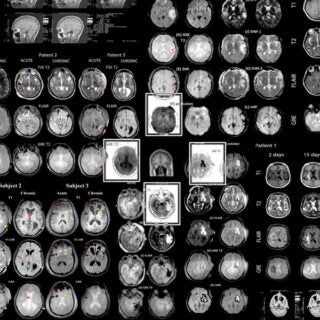

USC researchers are pushing the boundaries of what’s possible—using AI and genomics to personalize cancer treatment, advancing quantum computing for future breakthroughs, and uncovering a new way to fight brain cancer by targeting the body’s circadian clock. These discoveries reflect USC’s commitment to creating knowledge that drives progress in health, science and technology.

How AI and Genomics are personalizing cancer treatment